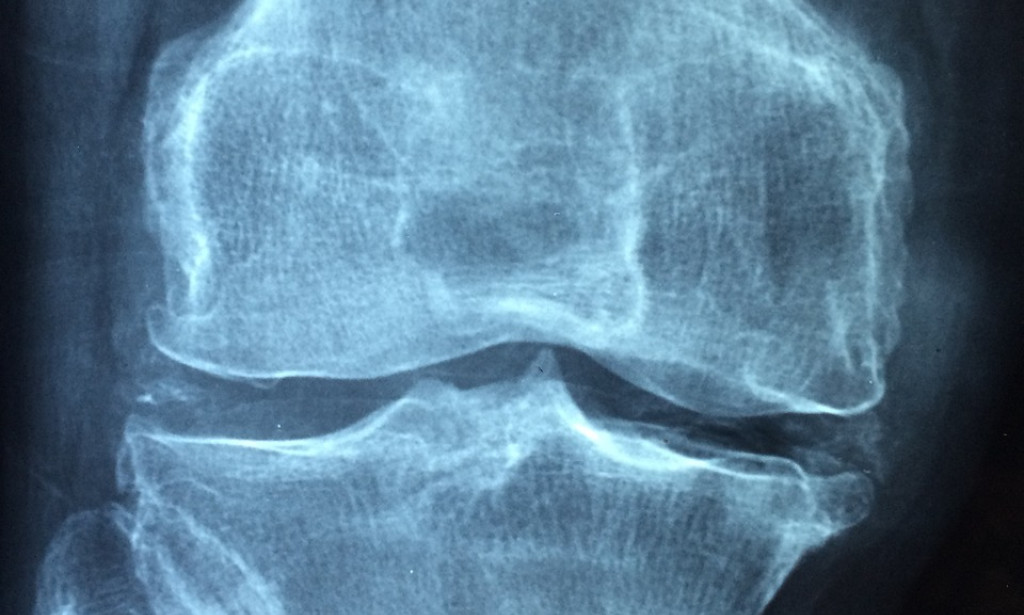

including rheumatoid part (RF) and against cyclic citrullinated peptide (threatening to CCP) antibodies, can help with attesting the end and assess disorder activity. Joint harm can be surveyed utilizing imaging instruments like X-beams, ultrasound, and attractive reverberation imaging (X-ray), as can illness movement over the long run. Rheumatoid joint pain treatment plans to reduce side effects, slow the movement of the infection, and improve in general capability and personal satisfaction. It is normal practice to recommend non-steroidal mitigating drugs (NSAIDs), corticosteroids, and infection altering antirheumatic drugs (DMARDs) for the reasons of controlling illness movement, diminishing aggravation and agony, and forestalling joint harm. Biologic subject-matter experts, for instance, malignant growth decay factor (TNF) inhibitors and interleukin-6 (IL-6) inhibitors, target express pieces of the safe structure drew in with the combustible cycle, offering additional treatment decisions for patients who don't answer enough to customary medicines.